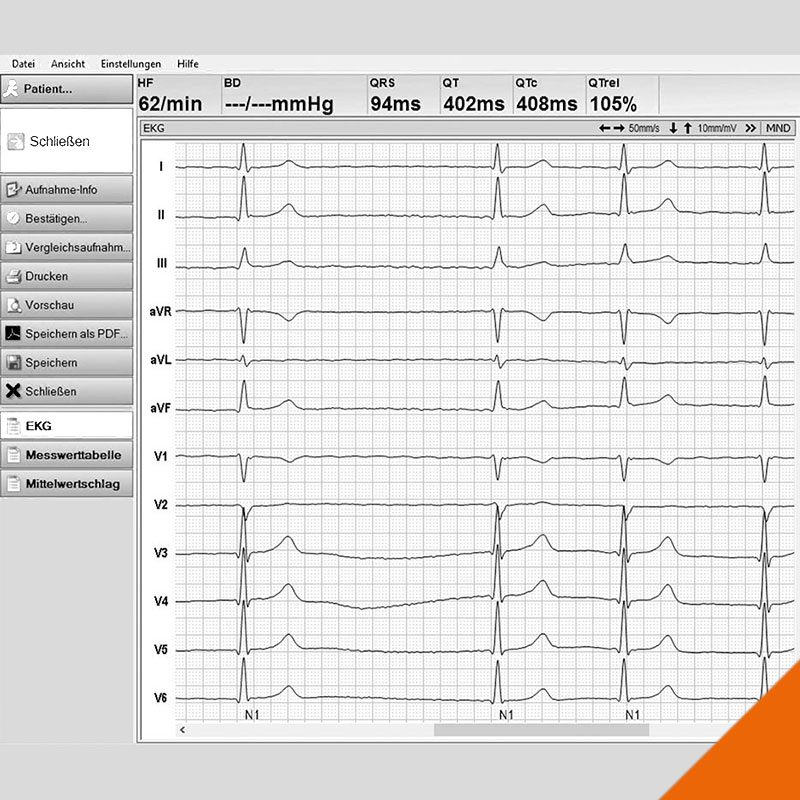

Kardiologie

Seit mehr als 20 Jahren widmen wir uns in unserer Praxis und in der klinischen Forschung der Früherkennung und Behandlung der Herzschwäche.